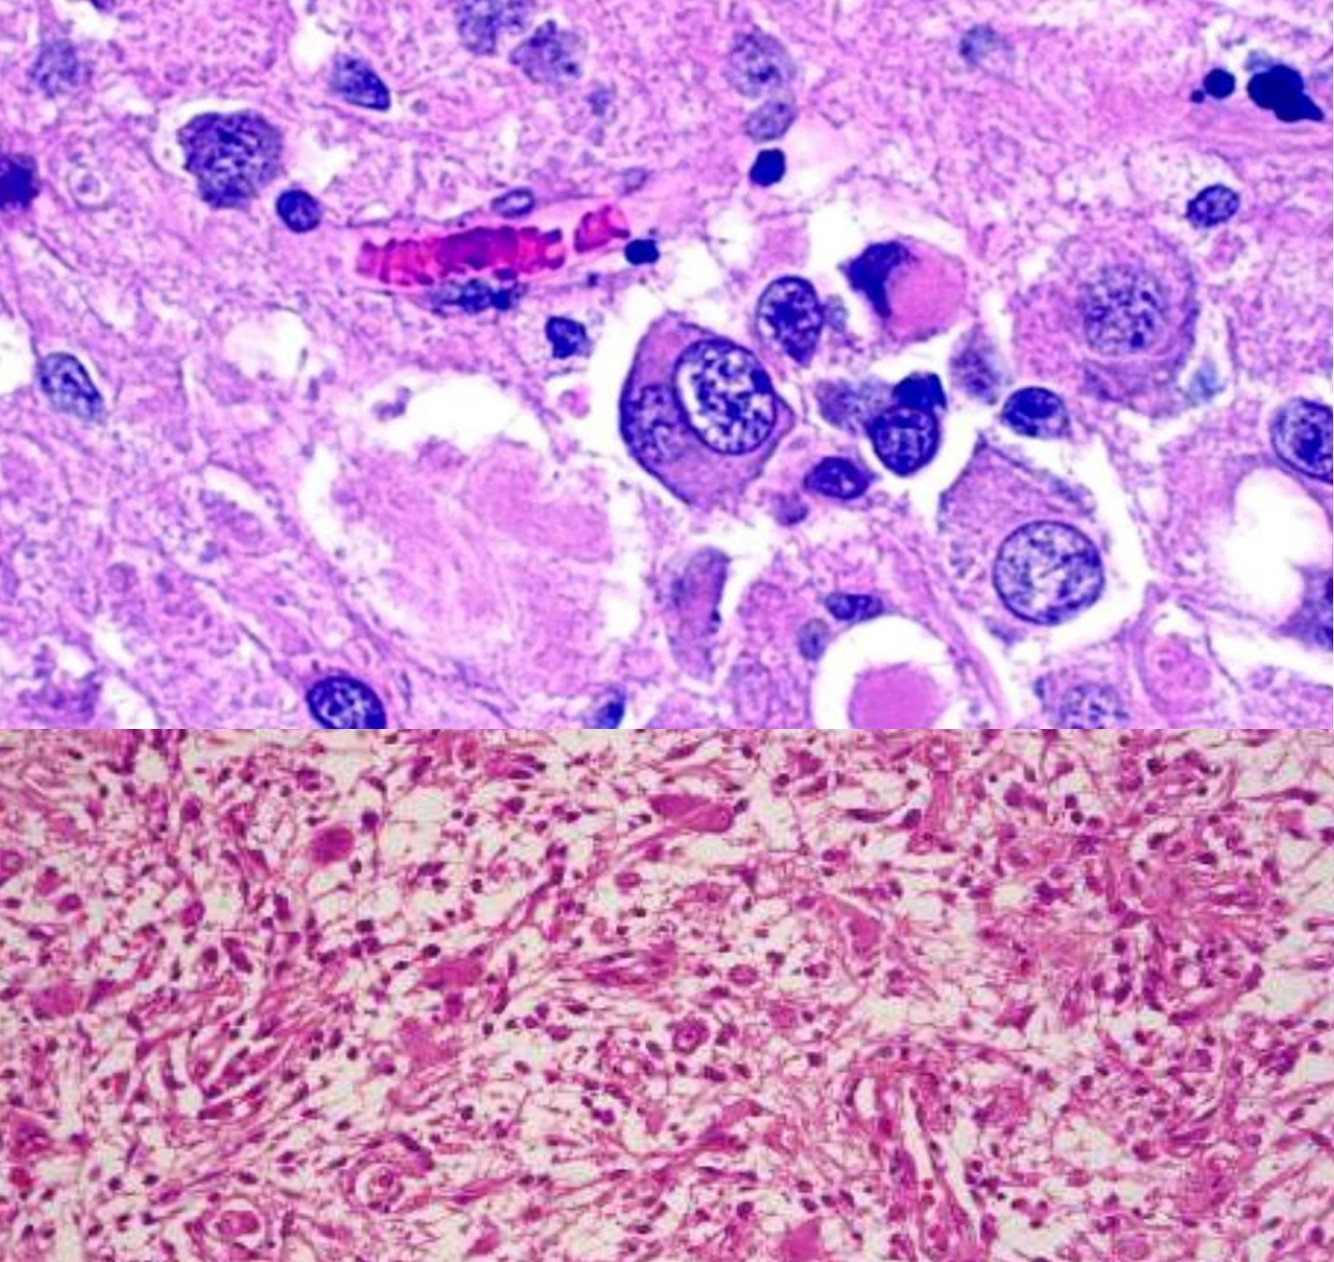

Glioblastoma, WHO grade IV

Astrocytic Genetics

Astrocytic Genetics

- Low Grade: p53 mutations and over expression of PDGF-A and its receptors

- Isocitrate dehydrogenase I (IDH 1), a metabolic enzyme in the citric acid cycle, is commonly mutated in astrocytomas, oligodendroglioma, and mixed gliomas- low grade (II) and anaplastic (III). Associated with better prognosis.

- Primary Glioblastomas: MDM2 amplification, mutated/ aberrant expression of EGFR/p16 deletion/ PTEN mutation

- Better response to chemotherapy: Methylation of promoter for gene encoding MGMT.

- 10q/PTEN deletion (e.g., whole-arm loss): predominantly astrocytic ‘signature’; comprises independent negative prognostic factor

- EGFR amplification (chromosome 7): evident in ‘primary’ glioblastomas (small-cell cytophenotype); comprises independent negative prognostic factor

Gemistocytic astrocytoma

- p53 positive

- Prone to progress to anaplastic and GBM